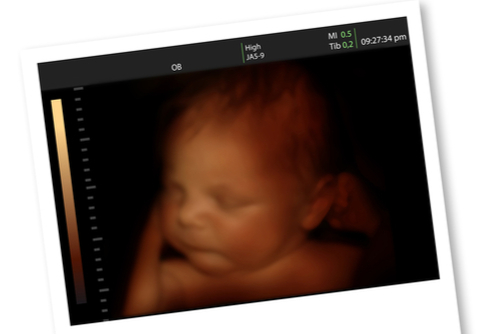

ダウン症児のエコー 誕生 告知 絶望 生まれた時の心境Down and UP。

妊娠中のエコー写真21枚で指摘できる、ダウン症の予兆東京・ミネルバクリニック。

医師監修 エコーでダウン症かわかるって本当?見え方や可能性があるときの対応を解説トモニテ。

エコー写真わかる?ダウン症の特徴 むくみ等 出生前診断のこころえ。

産婦人科医監修 4Dエコーでダウン症はわかる?鼻が低いと可能性あり?ダウン症の特徴が出る時期はいつ?ままのて。